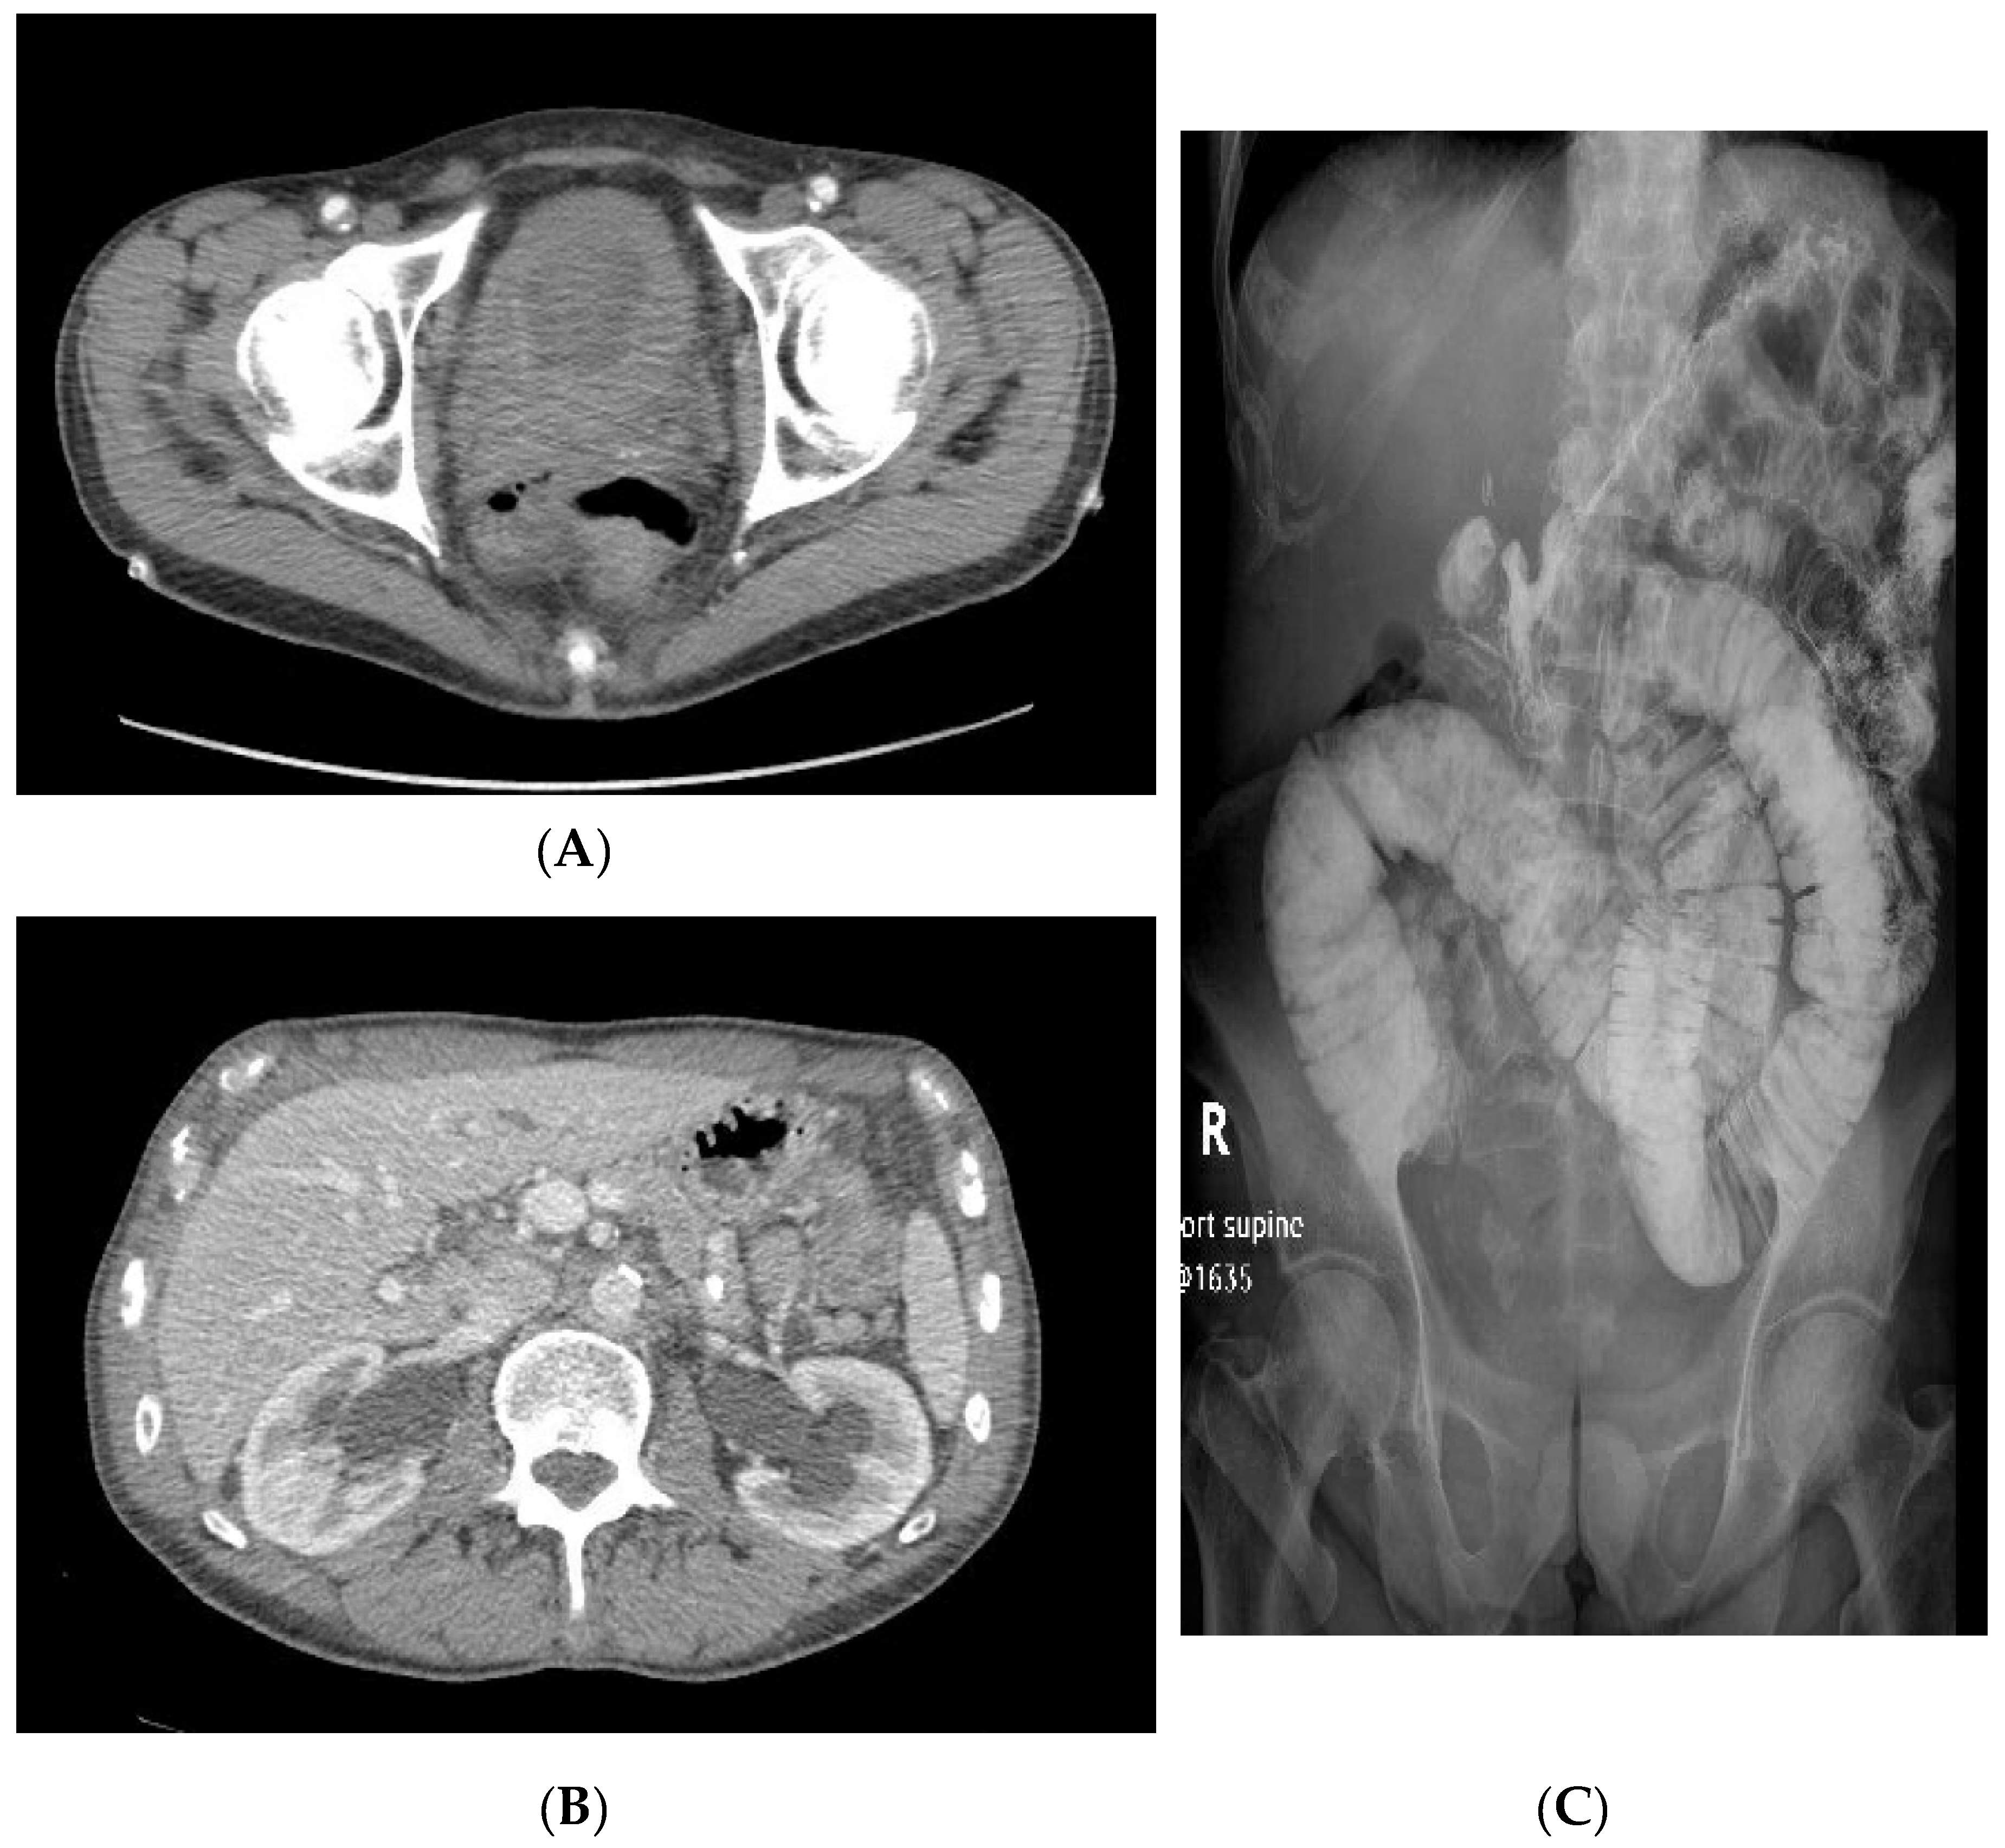

2. Case Series